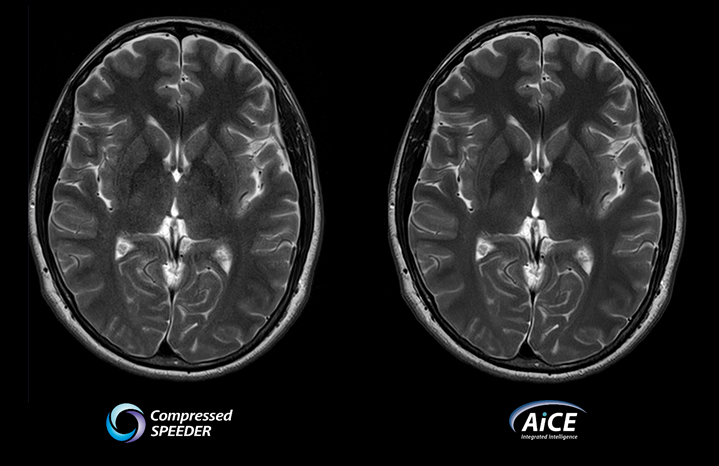

Совместите Compressed SPEEDER с AiCE DLR

• Увеличивайте разрешение за разумное время сканирования

• Улучшено качество изображения

• Повышенная клиническая уверенность

• Гибкость адаптации приобретения к текущей клинической задаче

• Увеличьте скорость или увеличьте отношение сигнал-шум и увеличьте разрешение

Сжатый SPEEDER против AiCE

Время сканирования 2:00

из Vantage Galan 3T